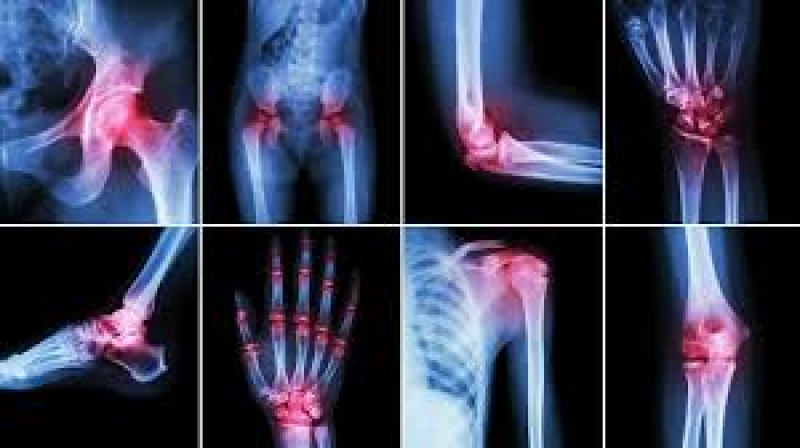

Diagnosis

Diagnosis often includes such medical investigations and tests, such as blood work analysis, x-rays, other imaging, after a thorough medical history and physical examination.